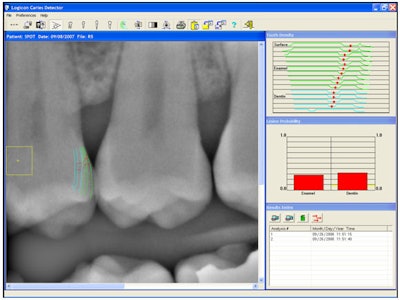

Now further analyzing the radiograph shows caries on the distal of No.12.

![]() |